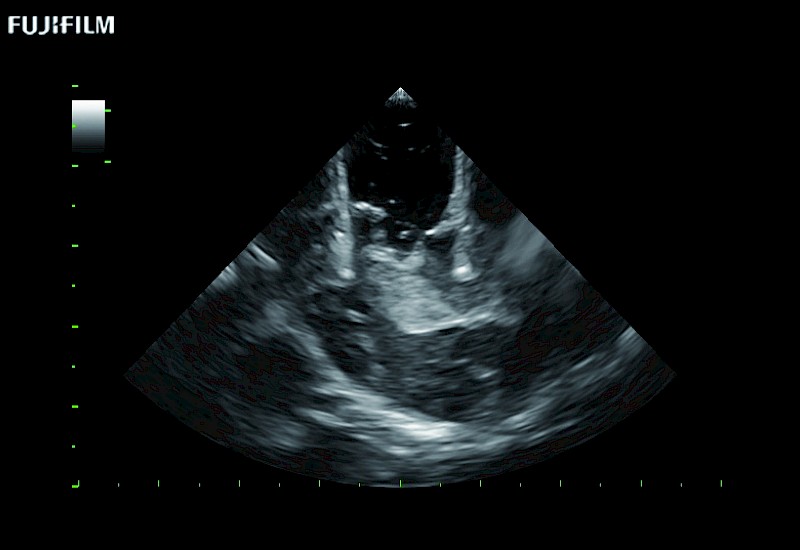

For precise neurosurgery ultrasound imaging, Fujifilm Healthcare offers premium level solutions that include:

Extraordinary high-resolution digital imaging

Our dedication to neurosurgery allows us to offer superior image quality, outstanding system reliability and intuitive use of cutting edge technology.